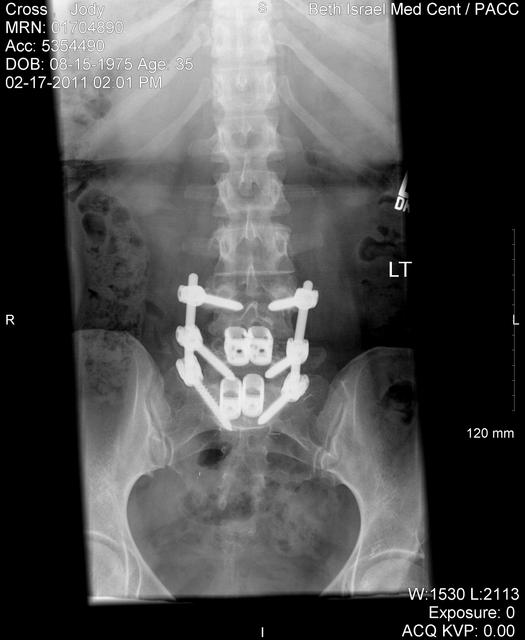

2010-01-26-04.jpg Date: 02/09/10 my favorite of the images, taken after the posterior portion of the surgery on 1/26/10, showing the titanium rods and screws, as well as the titanium cages that replaced the discs at L4-L5 and L5-S1. this one clearly and unquestionably demonstrates that i am, in fact, BIONIC ;)

2011-02-17-01.jpg Date: 02/22/11

2011-02-17-02.jpg Date: 02/22/11